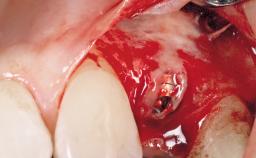

In 2004, a 36-year-old male patient, a non-smoker, presented due to acute pain in the premolar region of the upper left jaw. An orthopantomograph revealed that tooth 24 had been endodontically treated. It also became evident that, during root-canal filling,endodontic filling material had been pushed beyond the apex. This material was located very close to the maxillary sinus floor. Due to this finding in combination with the severe pain and a possible root fracture, tooth 24 was extracted. The esthetic expectations of the patient were not too high and his individual esthetic risk profile summed up to a medium risk profile.